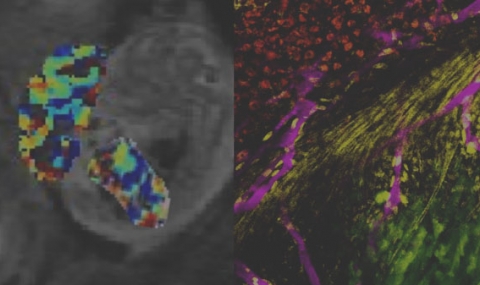

- Angiogenesis in ectopic ovarian xenotransplantation: Multiparameter characterization of the neovasculature by dynamic contrast-enhanced MRI

Israely T., Dafni H., Nevo N., Tsafriri A. & Neeman M. (2004) Magnetic Resonance in Medicine. 52, 4, p. 741-750

- Vascular remodeling and angiogenesis in ectopic ovarian transplants: A crucial role of pericytes and vascular smooth muscle cells in maintenance of ovarian grafts

Israely T., Dafni H., Granot D., Nevo N., Tsafriri A. & Neeman M. (2003) Biology of Reproduction. 68, 6, p. 2055-2064

- Non-invasive analysis of rat ovarian angiogenesis by MRI

Tempel-Brami C. & Neeman M. (2002) Molecular and Cellular Endocrinology. 187, 2-Jan, p. 19-22

- Spatial and temporal modulation of perfusion in the rat ovary measured by arterial spin labeling MRI

Tempel C. & Neeman M. (1999) Jmri-Journal Of Magnetic Resonance Imaging. 9, 6, p. 794-803

- Perfusion of the rat ovary: Application of pulsed arterial spin labeling MRI

Tempel C. & Neeman M. (1999) Magnetic Resonance in Medicine. 41, 1, p. 113-123

- Regulation of angiogenesis by hypoxic stress: From solid tumours to the ovarian follicle

- MODULATION OF WATER DIFFUSION DURING GONADOTROPIN-INDUCED OVULATION - NMR MICROSCOPY OF THE OVARIAN FOLLICLE